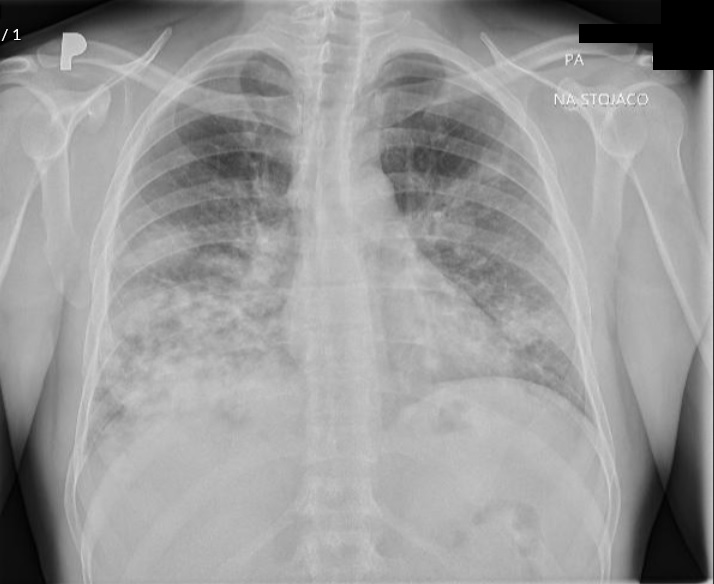

Case presentation: A 39-year-old man was initially diagnosed with lung cancer based on computed tomography and histopathologic findings. He was treated with 2 lines of chemotherapy over an 8-month period, the neoplastic lung lesions progressed, and he was referred to palliative care. Two years after his initial diagnosis, during the management of an actively bleeding gastric tumor, he was diagnosed with HIV and referred to an infectious disease unit. Immediate antiretroviral treatment was initiated after diagnosis, and further evaluation confirmed the presence of B-cell lymphoma. A retrospective review suggested that the initial cancer diagnosis was likely misinterpreted and was in fact lymphoma, a malignancy commonly associated with HIV. Lymphoma treatment was initiated, and after 1 year, the patient achieved HIV-1 virologic suppression and near-complete remission of all lesions.